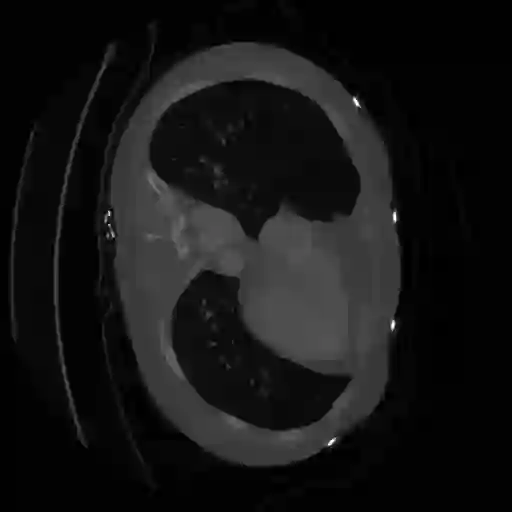

The integration of deep learning systems into healthcare has been hindered by the resource-intensive process of data annotation and the inability of these systems to generalize to different data distributions. Foundation models, which are models pre-trained on large datasets, have emerged as a solution to reduce reliance on annotated data and enhance model generalizability and robustness. DINOv2 is an open-source foundation model pre-trained with self-supervised learning on 142 million curated natural images that exhibits promising capabilities across various vision tasks. Nevertheless, a critical question remains unanswered regarding DINOv2's adaptability to radiological imaging, and whether its features are sufficiently general to benefit radiology image analysis. Therefore, this study comprehensively evaluates DINOv2 for radiology, conducting over 100 experiments across diverse modalities (X-ray, CT, and MRI). To measure the effectiveness and generalizability of DINOv2's feature representations, we analyze the model across medical image analysis tasks including disease classification and organ segmentation on both 2D and 3D images, and under different settings like kNN, few-shot learning, linear-probing, end-to-end fine-tuning, and parameter-efficient fine-tuning. Comparative analyses with established supervised, self-supervised, and weakly-supervised models reveal DINOv2's superior performance and cross-task generalizability. The findings contribute insights to potential avenues for optimizing pre-training strategies for medical imaging and enhancing the broader understanding of DINOv2's role in bridging the gap between natural and radiological image analysis. Our code is available at https://github.com/MohammedSB/DINOv2ForRadiology